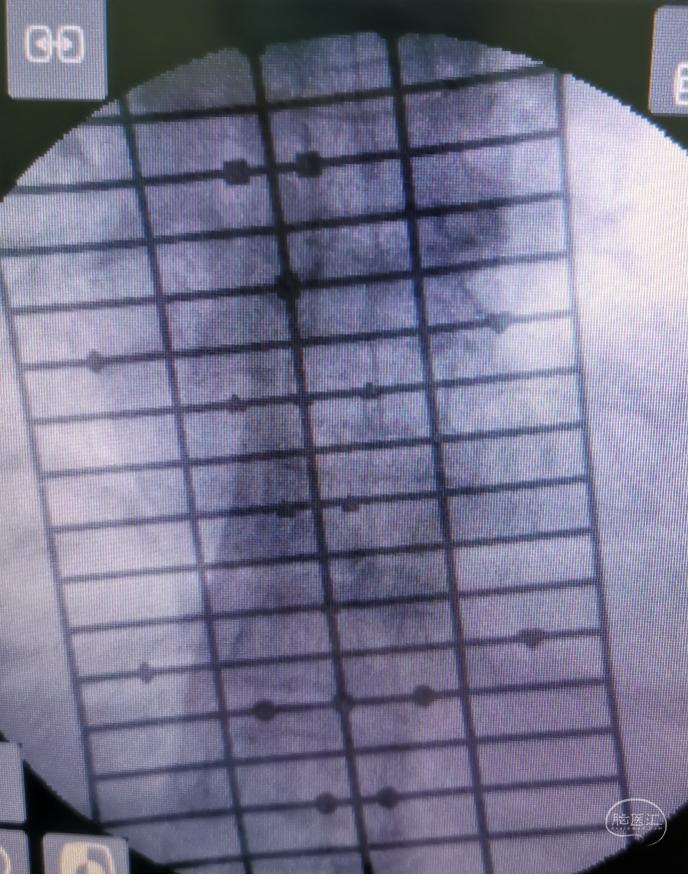

图2.胸椎内固定 图3.显露肿瘤

图3.显露肿瘤